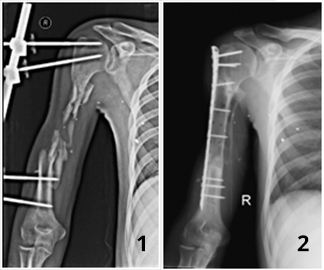

У хлопця в результаті кульового поранення утворився дефект правої плечової кістки на протязі до 15 см. За допомогою до нас звернувся через 15 місяців після поранення. До звернення проходив лікування в інших лікувальних установах, де будь-якої допомоги у відновленні дефекту кістки пацієнта надати не змогли.

Нами було проведено реконструктивно-відновне оперативне лікування з використанням клітинних технологій.

Через пів року в результаті проведеного лікування цілісність плечової кістки була відновлена ​​і пацієнт зміг повноцінно користуватися кінцівкою.